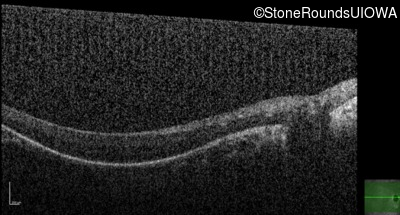

OD

OS

20/63 -1

OCT Stack

20/80